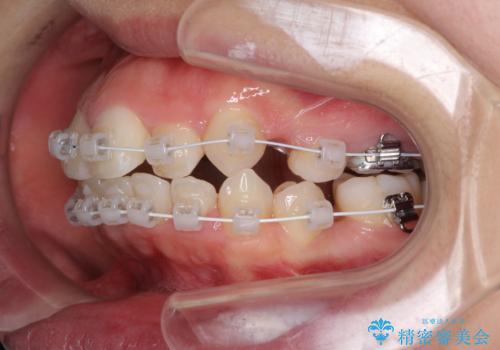

著しい叢生と顎骨のズレ ワイヤー装置による抜歯矯正

- 前歯の著しい叢生や八重歯を気にして来院された患者様です。

上下の顎がずれており、上下の正中は歯1本分の差がありました。

上下左右の小臼歯4本を抜歯し、極力正中を合わせるように矯正治療を始めていくこととしました。

咬み合わせの乱れが著しく、治療途中で一部反対咬合となってしまいました。

アンカーなどをうまく使用して、3年の期間を要してきれいに仕上げることができました。